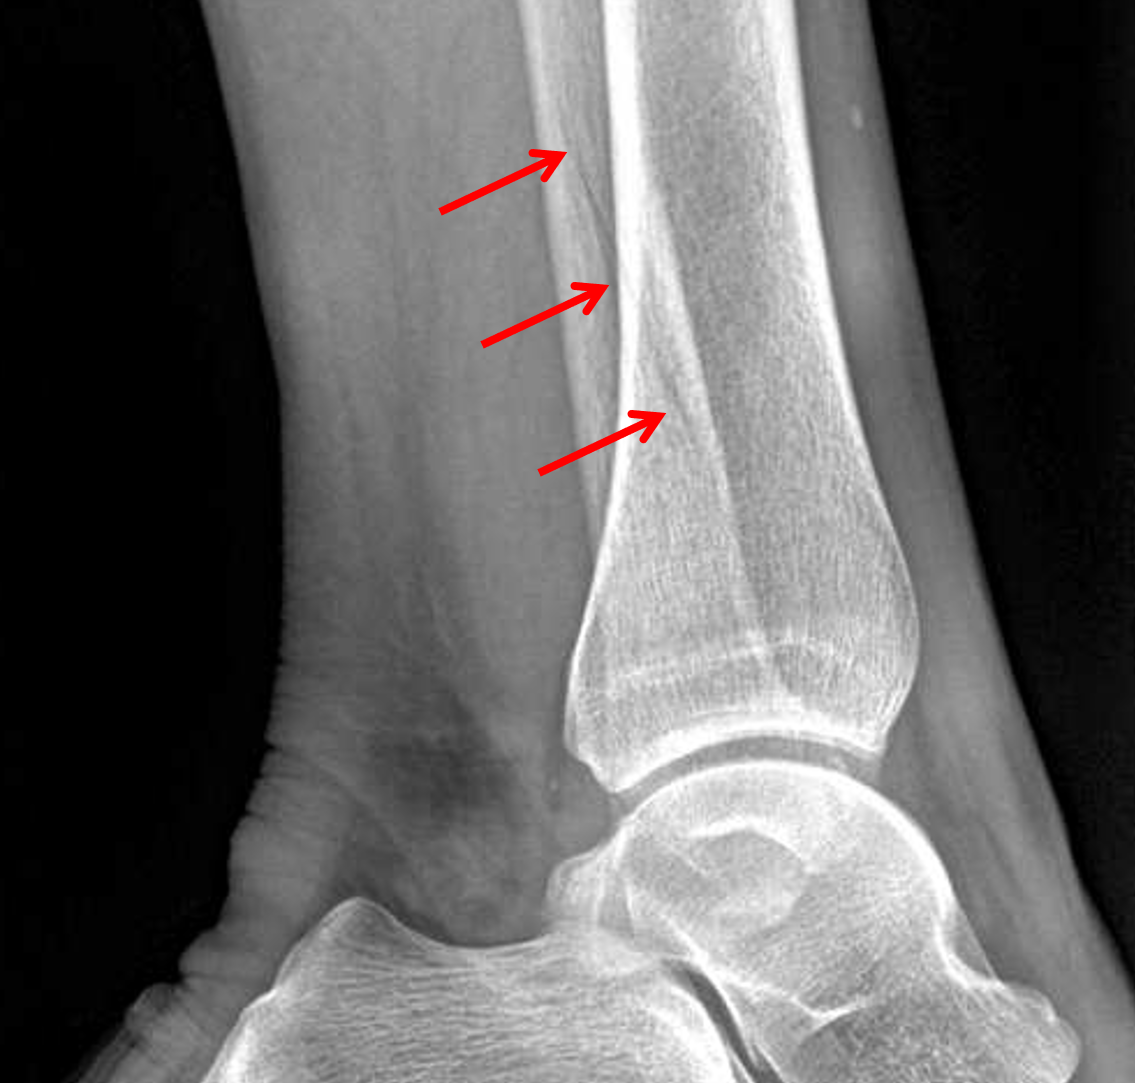

Age: 67

Sex: Female

Indication: Ankle injury

Sample ReportAcute nondisplaced oblique distal fibular diaphyseal fracture (Weber C).

Ankle mortise is congruent.

Mild degenerative changes of the tibiotalar joint.